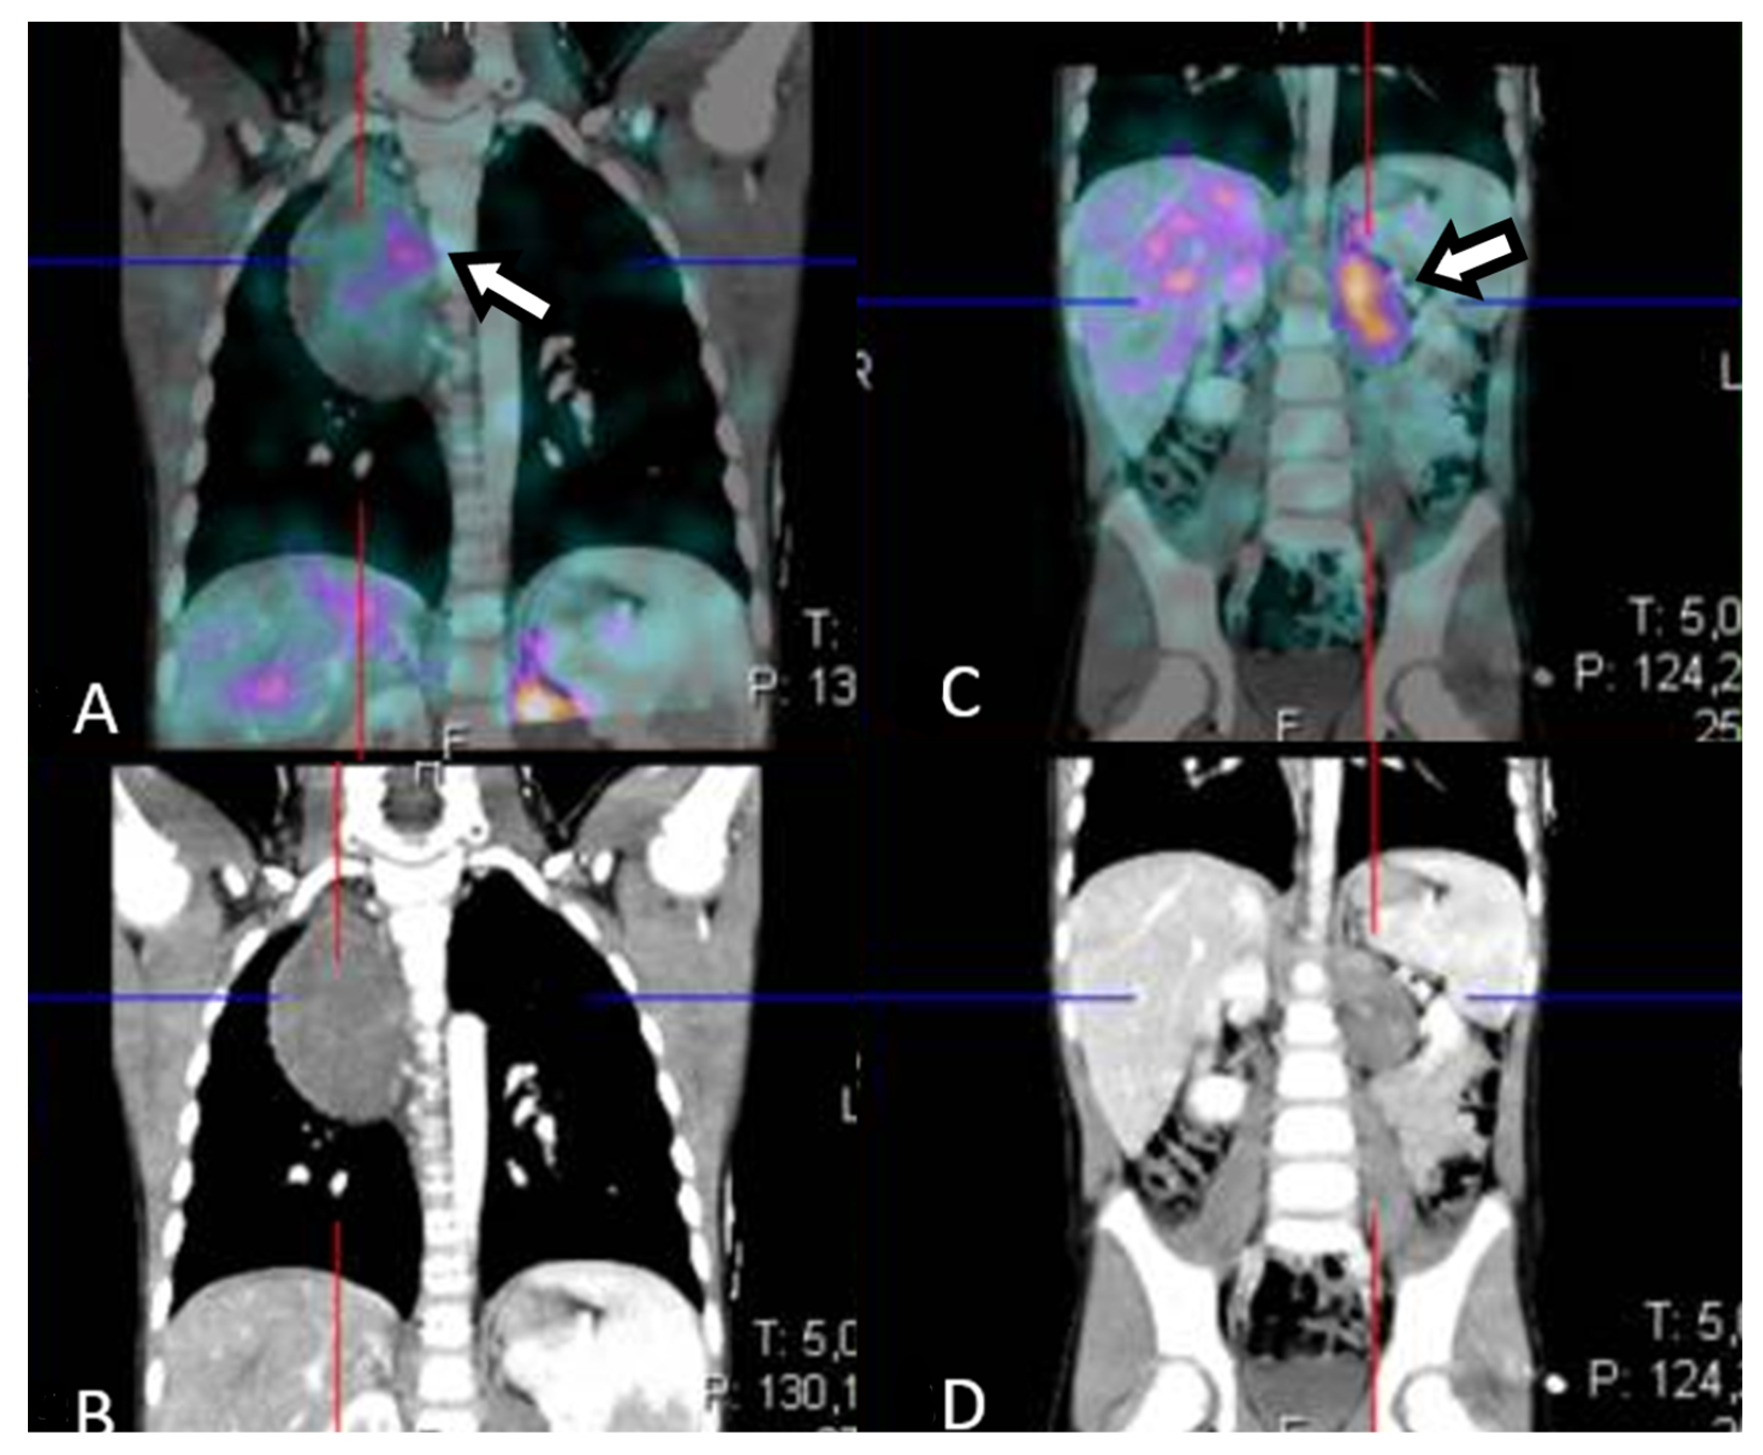

Figure 4. 18F-fluorodeoxyglucose/computed tomography (18F-FDG PET/CT) at one year from diagnosis. The patient was in good general clinical condition and the disease was stable; however, there were critical issues that were determined by the inability to rule out a nodular component within the already biopsied thoracic mass or the unstudied abdominal mass (see Figure 7). In order to characterize the metabolic activity of the mass, a 18F-FDG PET/CT scan was performed and showed FDG uptake in the left paravertebral mass (A) (maximum standardized uptake value -SUVmax-6.0), in the para-aortic lymph nodes (B) (maximum size 1.2 cm, SUVmax 5.8) and in the thoracic mass (C) (SUVmax2.3); no tracer uptake was detected in other sites. Tumor markers remained stable and within normal limits at all evaluations. The radiological and metabolic features assessed by 18F-FDG PET have not allowed the nature of the lesions to be clearly defined; in particular, with the available radiological investigations, the differentiation of benign and malignant NTs is quite controversial so far. Nevertheless, the different FDG uptake of abdominal lesions with lymph node involvements suggests a nodular component. In addition, the biopsy performed at onset may have been unrepresentative of the whole tumor, leading to late misdiagnosis with significant clinical fallout.